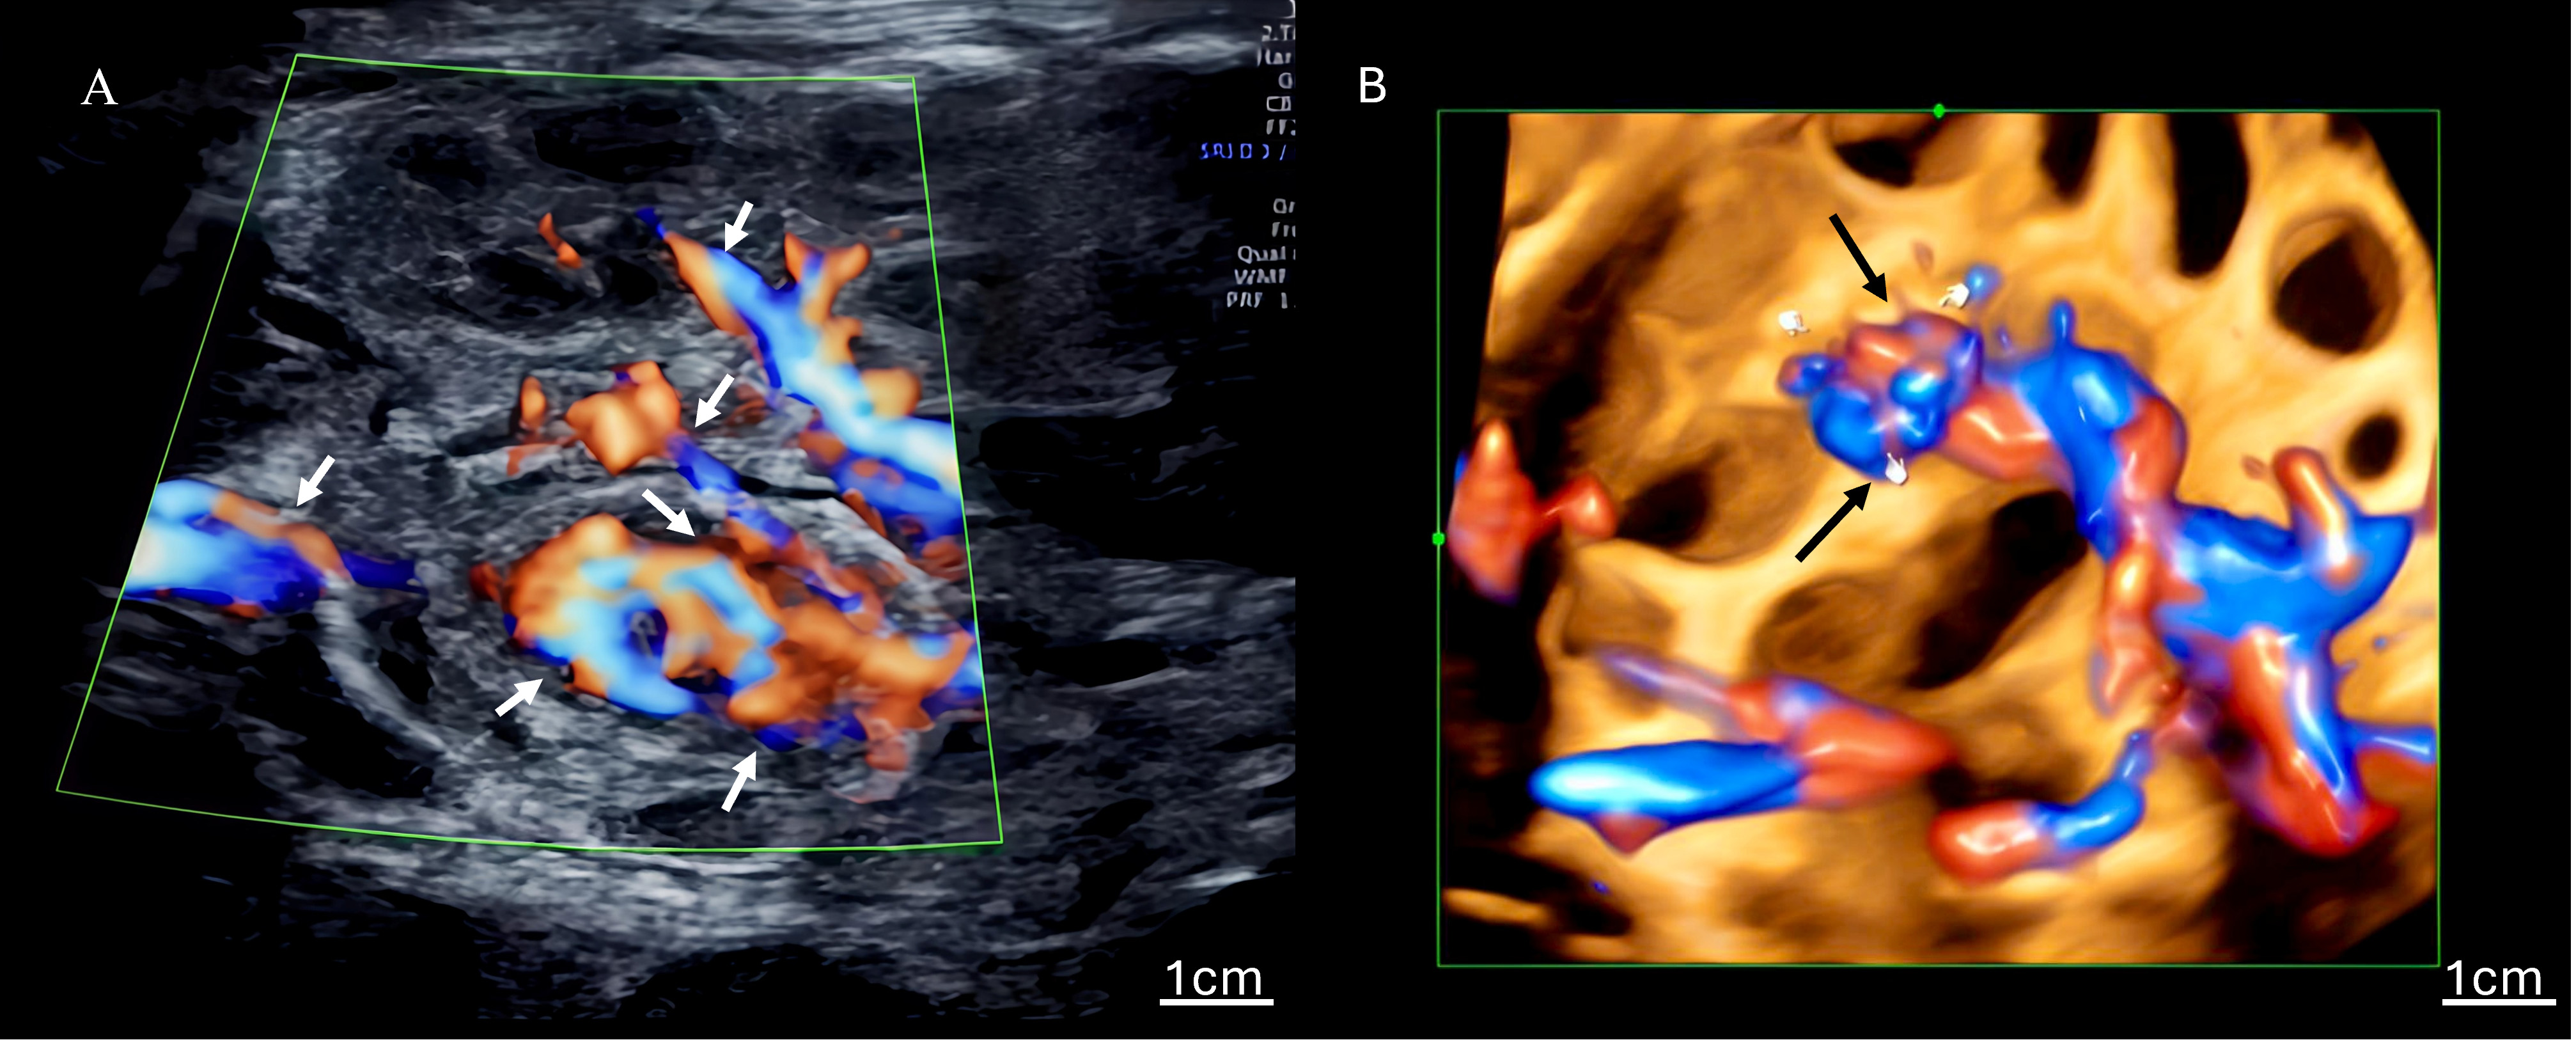

The ultrasonographic findings for all seven cases are summarized in Table 1, which details the gestational age at diagnosis and the presence of key signs. Table 2 quantifies the frequency of findings across all 27 examinations. Characteristic signs included the whirlpool sign (Fig. 1), annotated with arrows to highlight the spiral-shaped mass of dilated bowel loops), a spiral-shaped mass of dilated bowel loops, and the vascular spiral sign (Fig. 2A: 2D ultrasound; Fig. 2B: 3D ultrasound, with arrows indicating the mesenteric vein swirling around the mesenteric artery), observed in all cases (7/7). Nonspecific findings included bowel dilation (7/7), ascites (6/7), abdominal pseudocysts (2/7), coffee bean sign (2/7), hydramnios (1/7), and increased middle cerebral artery flow velocity (1/7). Among the 27 examinations, the detection rates were as follows: whirlpool sign, 20/27 (74.1%); vascular spiral sign, 20/27 (74.1%); bowel dilation, 23/27 (85.2%); ascites, 18/27 (66.7%); cystic abdominal masses, 5/27 (18.5%); coffee bean sign, 2/27 (7.4%); hydramnios, 3/27 (11.1%). Detailed case descriptions are provided below:

Fig. 2. Ultrasound images of the vascular spiral sign. (A) Two-dimensional color Doppler ultrasound of the vascular spiral sign, with the mesenteric vein swirling around the mesenteric artery, a direct indicator of volvulus; arrows highlight the swirling mesenteric vein, and a scale bar is included. (B) Three-dimensional power Doppler ultrasound enhances the visualization of the vascular spiral sign, observed in all cases. Arrows indicate the vascular spiral pattern, with a scale bar provided for reference. The little finger indicates the center of the whirlpool sign.